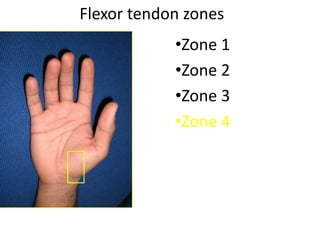

- It describes flexor tendon zones, extensor compartments, and pulley system anatomy.